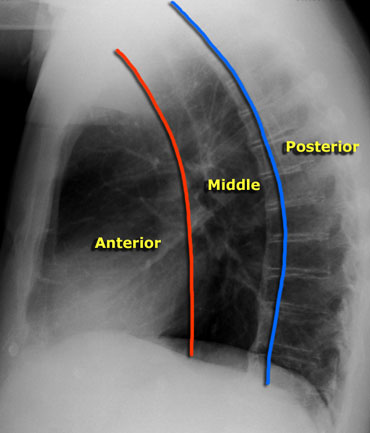

🛑Lateral xray confirms the lesion is in posterior mediastinum

♓️Lateral border of the opacity is >2cm from the hilar vessels&not converging towards the vessels (Hilum convergence sign-ve) s/o the lesion is not in middle med

❇️Inferior border of the opacity extend below R.diaphrgm s/o lesion in post med as ant med doesn’t extend below it Image